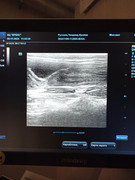

Сделали повторное узи 22.11. 2024 (первое было 09.11.2024). Высылаю фото и заключение.

Теперь ставят гидрометру и эндометрит. По мочевому мочекаменную.